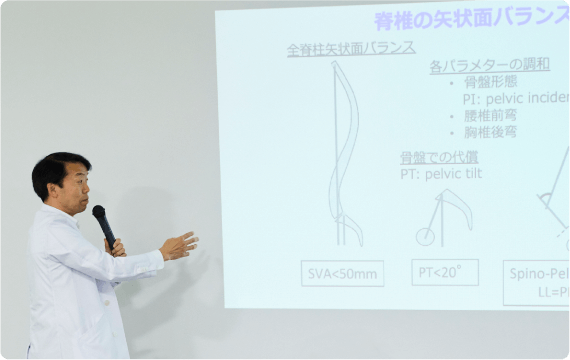

脊椎

患者さまの高齢化に伴い、脊椎疾患に対しても集学的な治療が必要となっております。整形外科医のみで治療するのではなく、内科医や外科医、麻酔科医が患者さまの治療に協力して参加することにより、全身状態の正確な把握と管理、合併症の早期発見と早期治療、術後疼痛の少ない手術、早期リハビリテーション介入、早期退院が可能となっております。

もう一つの特徴である回復期病棟・緩和病棟との連携によって、脊柱変形に対する大きな手術を受けられた患者さまや高齢ゆえに術後回復に時間を要する患者さまに対し回復期病棟・緩和病棟において、ゆっくり・じっくりとリハビリテーションに励んでいただき、自宅退院を目指していただくという環境が整っております。